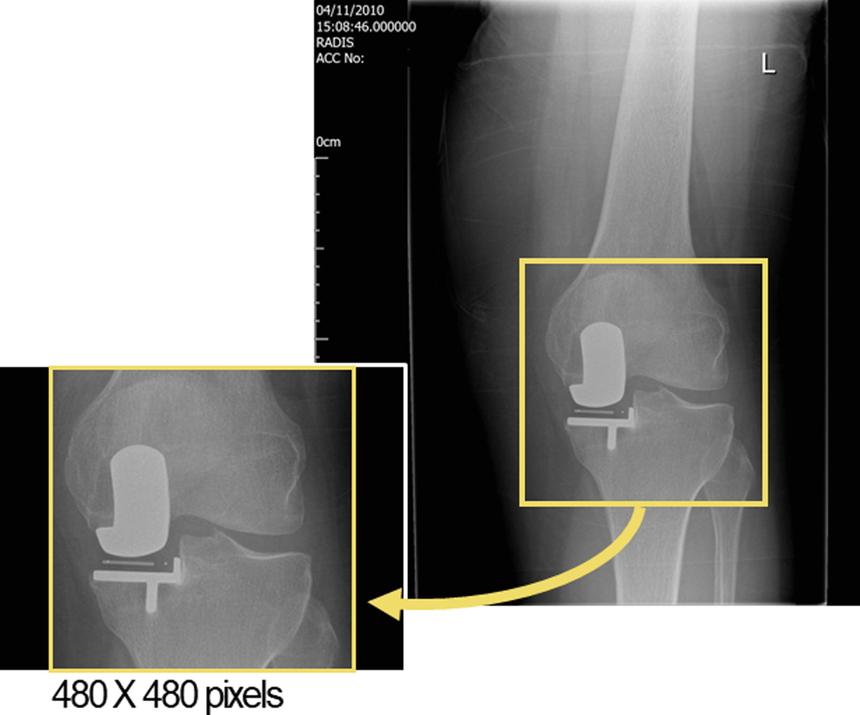

Исследование, проведенное в NDORMS и опубликованное в журнале The Knee, показало, что ИИ может выявить паттерны, которые обычно незаметны для врачей. В рамках эксперимента специалисты обучили модель машинного обучения анализировать рентгеновские снимки, чтобы предсказать, у кого из пациентов будет плохой исход после операции.

Команда проанализировала более 900 рентгенов, сделанных через год после операции, и сравнила прогнозы хирургов с результатами ИИ. Модель машинного обучения предсказала плохие результаты в 71% случаев, в то время как хирурги смогли правильно определить их только в 0−7% случаев.